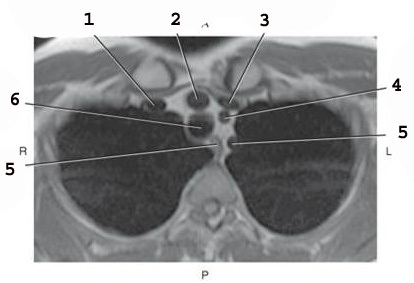

1

Rt brachiocephalic vein

2

brachiocephalic artery

3

L brachiocephalic Vein

4

L common carotid A

5

L subclavian artery

6

trachea

5 on the left

esophagus (there are 2 number 5’s)